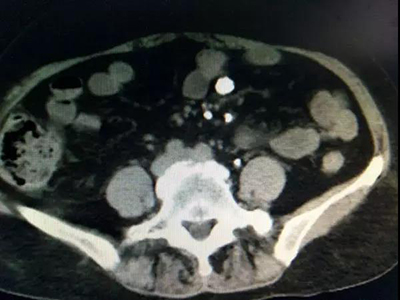

入院后彩超檢查顯示:左腎竇內(nèi)可見數(shù)個大小不等的結(jié)石,最大的2.6 x1.9厘米,左輸尿管上段距腎門2.5厘米處可見一大小約1.9厘米的結(jié)石。腎盂靜脈造影顯示:左腎及左側(cè)輸尿管上段多發(fā)結(jié)石,伴左側(cè)腎盂、腎盞擴張;右腎缺如。CT檢查顯示:左腎腎盂、腎盞多發(fā)不規(guī)則高密度影,部分形成腎盞鑄型,邊緣銳利,CT值780—1500HU,左腎多發(fā)類圓形低密度影,右腎缺如。心電圖檢查:T波改變。胸片提示:兩肺紋理增多、心影增大。經(jīng)詳細檢查最終確診為:左腎多發(fā)結(jié)石、左輸尿管多發(fā)結(jié)石、左腎多囊腎、右腎缺如、高血壓Ⅱ級。